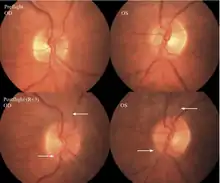

The first U.S. case of visual changes observed on orbit was reported by a long-duration astronaut that noticed a marked decrease in near-visual acuity throughout his mission on board the ISS, but at no time reported headaches, transient visual obscurations, pulsatile tinnitus or diplopia (double vision). His postflight fundus examination (Figure 1) revealed choroidal folds below the optic disc and a single cotton-wool spot in the inferior arcade of the right eye. The acquired choroidal folds gradually improved, but were still present 3 year postflight. The left eye examination was normal. There was no documented evidence of optic-disc edema in either eye. Brain MRI, lumbar puncture, and OCT were not performed preflight or postflight on this astronaut.[5]

Figure 1:Fundus examination of the first case of visual changes from long-duration spaceflight. Fundus examination revealed choroidal folds inferior to the optic disc and a single cotton-wool spot in the inferior arcade of the right eye (white arrow).

Figure 2: Fundus examination of second case of visual changes from long-duration spaceflight. Fundoscopic images showing choroidal folds (white arrows) in the papillomacular bundle area in the right eye and left eye and a cotton-wool spot (bottom arrow) at the inferior arcade in the left eye. Both optic discs show grade 1 disc edema.